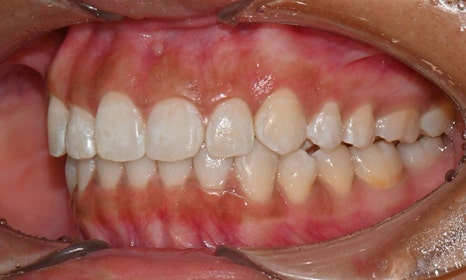

위아래 앞니 사이가 벌어져서 공간이 있었고, 앞니에 약간씩 배열이 틀어진 덧니가 있었습니다. 정면에서 보았을 때 윗니와 아래 앞니가 깊게 물려서 아래 앞니가 잘 보이지 않는 과개교합 양상을 보이고 있었습니다. 또한 왼쪽 아래 작은 어금니가 90도 앞으로 돌아가서 좌측 치아 배열 및 교합이 좋지 않은 상태였습니다.

초진시 구내사진 (2025. 3.31)